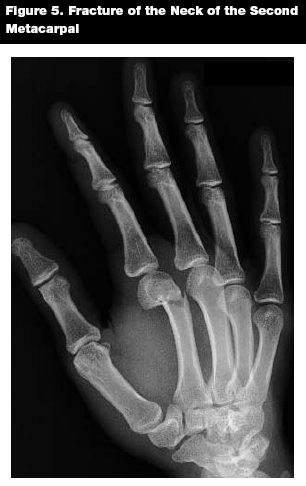

Patterns of Injury. Metacarpal fractures often result from athletic injuries in pediatric patients.21 Metacarpal fractures can be divided into fractures of the neck, head, shaft, and base. (See Figure 5.) Fractures of the metacarpal neck are the most common, and most often involve the small and ring finger,22 with fractures of the neck of the fifth metacarpal representing 80% of pediatric metacarpal fractures in one series.16 These fractures often occur when a closed fist strikes an object.23 Metacarpal head fractures, which can result from direct trauma and axial loading, often involve the joint, leading to late complications such as arthritis.20,22

![]() |